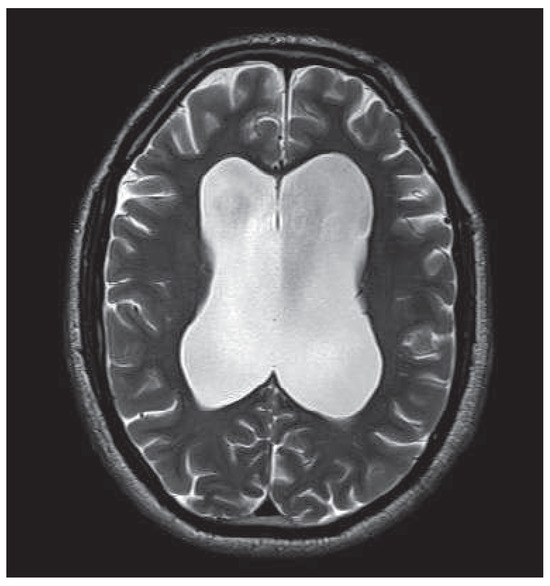

Hydrocephalus, psychosis and art: a case report

by Sarah Noll, Heinz Boeker, Gerold Roth-Greminger, Paul Hoff and Daniel Schuepbach

Objectives: Published evidence suggests a linkage between structural brain damage and psychotic symptoms. Internal hydrocephalus often manifests with neurological and psychiatric symptoms, which occur with great variety between individuals. Methods and results: We present a case of a male suffering from treatment refractory psychosis for years, and with a special talent for artistic painting. An enormous communicating hydrocephalus, which has probably existed for several years, was detected by means of anatomical neuroimaging. As the patient began to suffer from signs of high intracranial pressure such as headache and dizziness, an endoscopic third ventriculostomy was successfully performed. The neurological symptoms disappeared shortly after surgery, psychotic symptoms attenuated gradually and artistic work changed. Conclusions: This case is exceptional with regard to symptoms caused by a hydrocephalus and changes in artistic work, as an expression of executive function and abstract thinking, due to surgical intervention. It demonstrates the need to pay attention to cerebral lesions when confronted with neuropsychiatric symptomatology, especially if psychotic symptoms persist despite adequate antipsychotic treatment. Full article

Figure 1